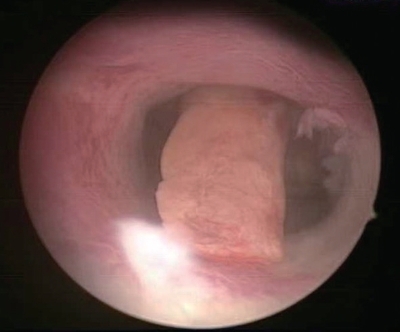

3)子宫黏膜下肌瘤:呈球形或椭圆形,突出于子宫腔内,覆盖内膜,较苍白,可见较粗的树枝状血管或走行规则的网状血管。数量、根蒂情况因人而异(图3-11)。